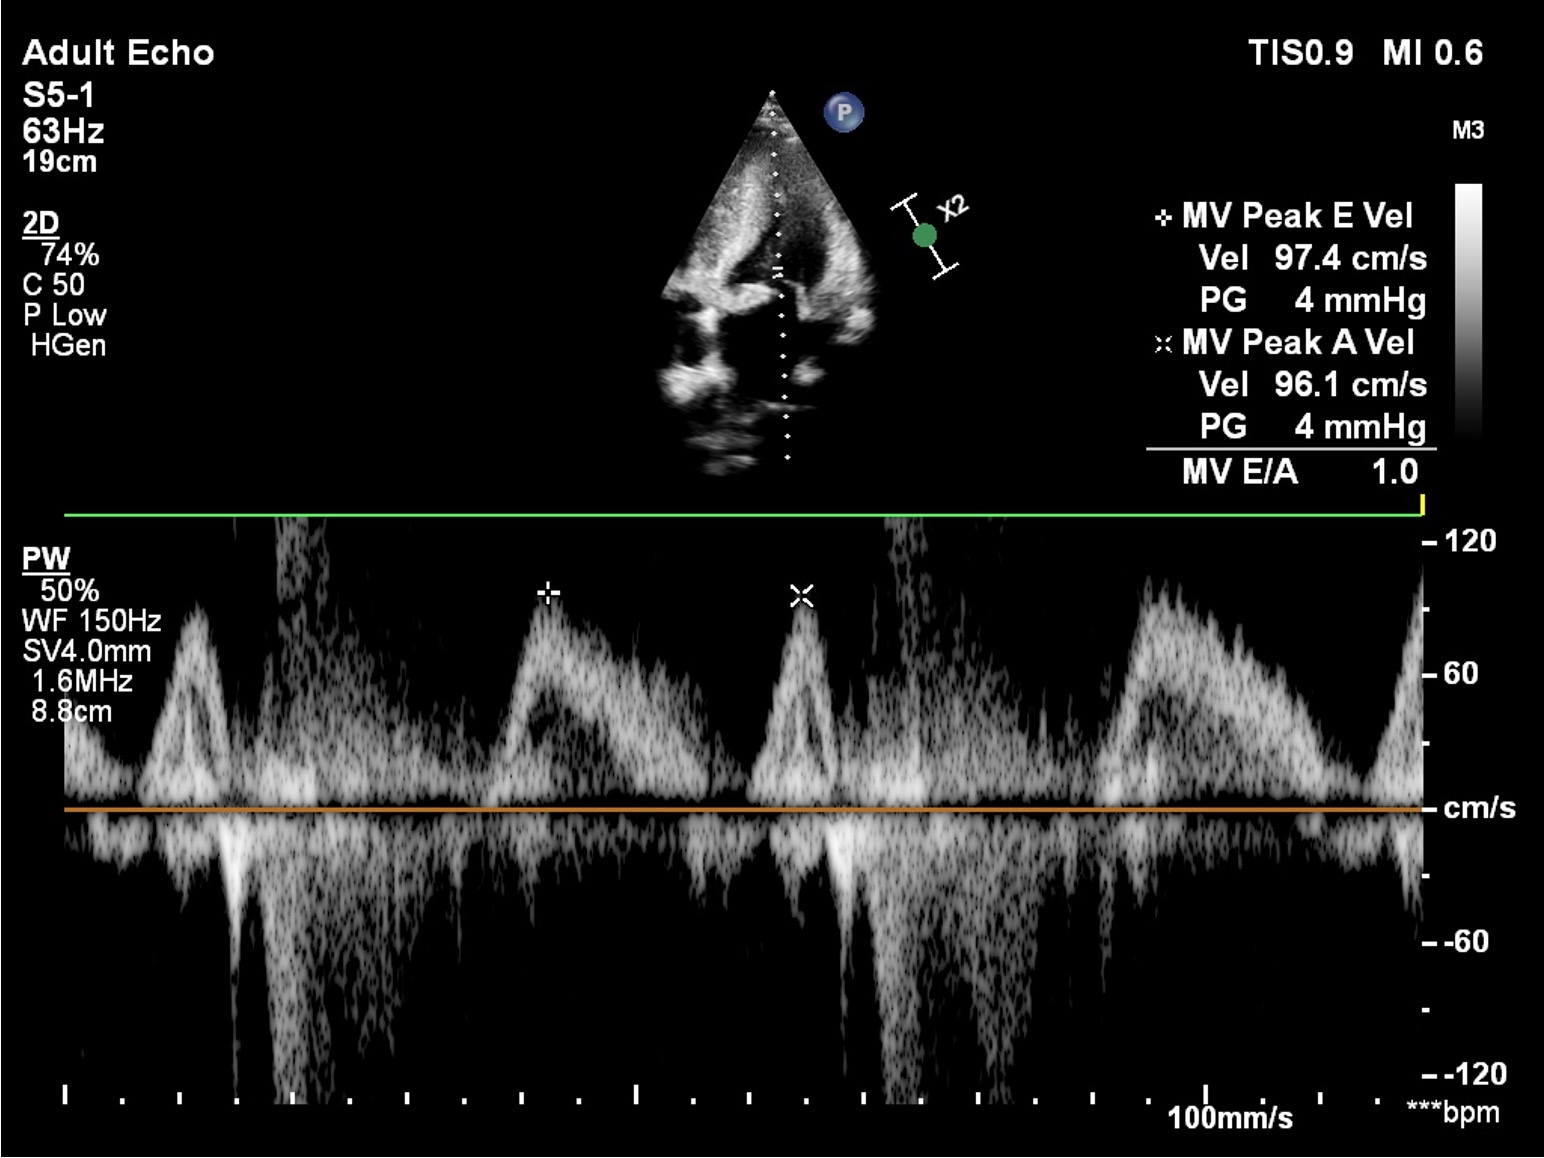

Description of Case: A 30-year-old South Asian male presented with exertional chest pain and dyspnea, classified as New York Heart Association (NYHA) Class II. Clinical examination revealed multiple cutaneous neurofibromas, indicative of NF1. Electrocardiography (ECG) demonstrated left ventricular hypertrophy, while echocardiography confirmed the presence of asymmetric septal hypertrophy and systolic anterior motion (SAM) of the mitral valve, findings consistent with hypertrophic cardiomyopathy (HCM) and left ventricular outflow tract obstruction. Laboratory investigations revealed severe iron-deficiency anemia, attributed to alcohol-related malnutrition. Familial screening indicated that his mother and sister, both positive for NF1, also exhibited asymptomatic HCM on echocardiography. This familial clustering underscored the syndromic nature of his condition. The patient was initiated on guideline-directed medical therapy, alongside lifestyle interventions targeting anemia and alcohol cessation.